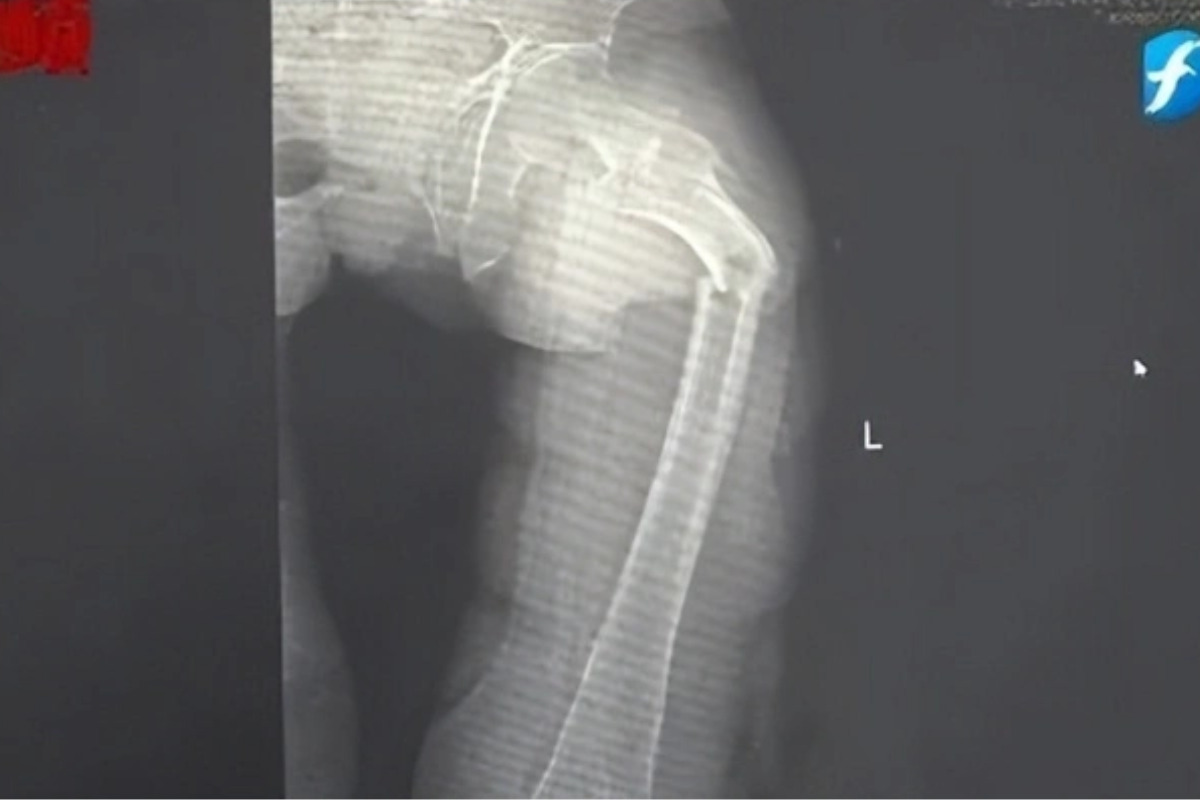

Đến nửa đêm, anh Cung bị giật mình tỉnh giấc vì cơn đau ở đùi. Anh phát hiện ra mình không thể đi lại được nhưng cố chờ đến trời sáng hẳn rồi nhờ người nhà đưa đi bệnh viện. Kết quả chụp X-quang tại Bệnh viện Nhân dân số 2 Phúc Kiến (Trung Quốc) khiến anh Cung sốc nặng: xương đùi trái của anh bị gãy làm hai mảnh.

Bác sĩ Đông Trung, Trưởng khoa Chấn thương và Chỉnh hình của bệnh viện cho biết anh Cung bị gãy xương bệnh lý, xảy ra do loãng xương sớm rất nghiêm trọng. Dù mới 35 tuổi nhưng xương của anh Cung được bác sĩ nói vui là "xốp như tổ ong", khối lượng xương tương đương với một cụ già 80 tuổi.